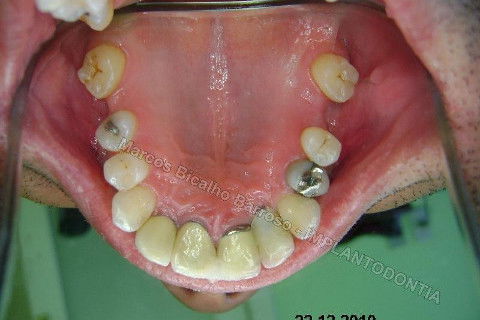

Este caso tem o objetivo de demonstração da técnica que normalmente sigo ; em casos onde ocorre fratura da raiz e consequentemente abscessos, com ou sem formação de fístula. Neste caso fiz a exodontia com preenchimento do alvéolo com biomaterial (osso bovino liofilizado + coágulo do paciente). Após 90 dias, mais ou menos, instalei o implante. Esperei mais 4 meses e realizei ontem (12/11/2010) a instalação do cicatrizador com o cuidado de preservar tecido mole, sem remoção de material, apenas afastando gengiva e "enrolando" a sobra de mucosa em direção a face vestibular, para promover conservação de papila futuramente. Se ocorrer excesso de papila, sem problema, remove-se um pouco, mas a intenção é não deixar faltar, o que resultaria em indicação para enxertos gengivais.